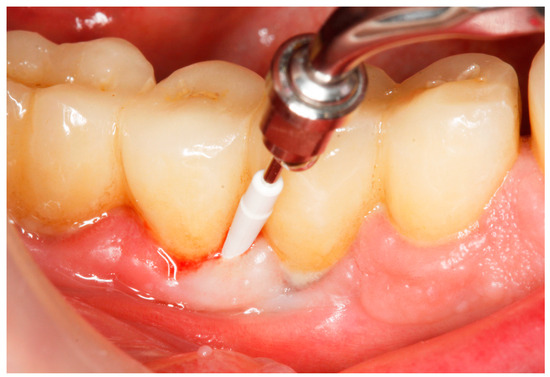

2.8. Treatment Procedures

- PMPR, individualized OH recommendations, for entire dentition/implants;

2.9. Evaluation of Treatment Effect